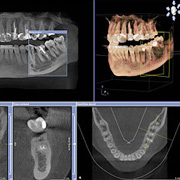

Digitaler Volumentomograph (DVT)

Ein digitaler Volumentomograph (DVT)ermöglicht dreidimensionale Aufnahmen des knöchernen Gesichtsschädels. Mit den gestochen scharfen 3-D-Ansichten können wir die knöchernen Strukturen des Oberkiefers und des Unterkiefers, ausgesuchte, einzelne Segmente oder komplexe Zusammenhänge detailliert darstellen. Diese neue Technik eröffnet der Zahnmedizin zuverlässige diagnostische und therapeutische Möglichkeiten in der Implantologie, Prothetik, Kieferorthopädie und Zahnerhaltung. Schon vor einem Eingriff werden Knochenangebot, Knochenqualität und individuelle Besonderheiten erkannt. Ein weiterer Vorteil der digitalen Volumentomographie ist die deutlich geringere Strahlenbelastung gegenüber der bekannten Computertomographie.